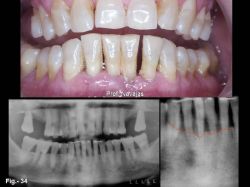

Caso nº 4 Mujer de 62 años que acude a consulta para tratamiento de la movilidad de sus dientes inferiores. De su exploración clínica y radiográfica se diagnóstica como periodontitis crónica del adulto con pérdida de soporte óseo. Los incisivos inferiores son inviables. En la Fig. 34 se puede apreciar la situación clínica y radiográfica de la paciente. Se decide exodoncia de los incisivos inferiores y la colocación de dos implantes inmediatos en situación 32 y 42, para la reposición inmediata de la estética. Durante la implantación, se coloca injerto de Bio-Oss GeistlichnBiomaterials en los alvéolos de 31 y 41, para el mantenimiento de la cresta alveolar. En las figuras 35 y 36 se puede observar la secuencia clínica de la implantación y reposición protética y en la 37 el resultado después de más de 4 años de la implantación.  | |  | | Fig. 34: Situación clínica y radiográfica de la paciente. El aspecto de los tejidos blandos, la apertura de diastemas y la pérdida de soporte óseo ponen de manifiesto la inviabilidad de los incisivos inferiores. | | Fig. 35 a y b: En (a) se observa la situación de los dos implantes Q TrinonR de 3.5 por 14mm de longitud, colocados tras la exodoncia de los incisivos. En (b) la prótesis fija provisional recién colocada. Para mantener la arquitectura de la cresta se colocó un injerto de Bio-Oss Geistlichn Biomaterials en los alvéolos de 31 y 41. | | | | |  | |  | | Fig. 36 a y b: En (a) aspecto de los implantes y tejido gingival antes de colocar la prótesis fija; en (b), la prótesis definitiva recién colocada. La pequeña zona irritada del 32 es debida a sobredimensión de la corona acrílica provisional. | | Fig. 37 a y b: En (a) aspecto de la prótesis definitiva a los cuatro años y cinco meses; en (b), aspecto radiográfico de los implantes a los cuatro años y cinco meses de su inserción. Obsérvese la buena situación de los implantes y la zona del injerto de Bio-Oss Geistlichn Biomaterials en 31-41 |